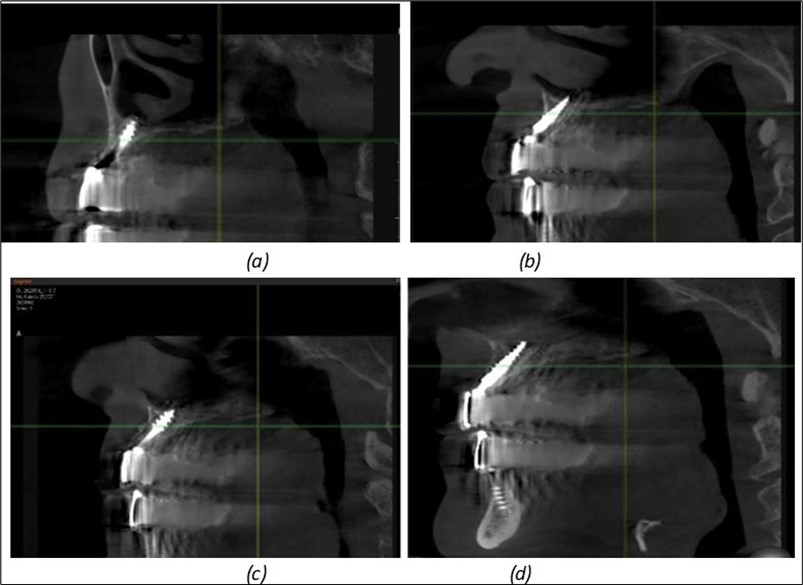

A total of 11 implants is placed in the maxilla, including compressive TPG implants with a polished surface in the maxillary-sphenoid fusion area (Figure 3, Figure 9). Similarly, in the anterior region, final fixation is achieved in the nasal cortex, and BCS corticobasal implants are added in areas with massive bone loss in the frontal region (Figure 3, Figure 8, Figure 11). Additionally, in the palatal sinus cortical area, with the aim of avoiding the addition and sinus lift zone where the second cortical bone no longer exists, 3 implants are placed, 2 in quadrant 1 and 1 in quadrant 2 (Figure 3, Figure 8). Through the Caldwell-Luc sinus lift procedure, the sinus cortical bone is displaced to allow the placement of the graft material and elevation of the sinus membrane. This sinus cortical is no longer recreated at the junction of the graft material and mucosa-sinus membrane, making it impossible to place a corticobasal implant, which relies on the second cortical bone. In the distal mandibular area, after the removal of two stage implants due to massive destruction in quadrant 3, implant placement distal to the mylohyoid line is not possible, as in quadrant 4 (Figure 10). A re-intervention occurs after 5 months to stabilize the area (Figure 12, Figure 14). Also, at the moment of fixation, the tip of one implant fractures, and the decision is made to leave it in place due to regional bone destruction, in order to avoid enlarging the bone defect.

Figure 14.Rx panoramic final situation control: (a) Panoramic X-ray with the addition of a distal BCS implant in quadrant 3 at 11.2022; (b) Control X-ray, 10.2023.

The results of rehabilitation treatment with corticobasal and compressive implants with a polished surface after the failure of two stage implants were highlighted over a period of 3 years and 3 months as being very good (Figure 14, Figure 15), with the patient completing a satisfaction survey in this regard. Certainly, it is necessary to continuemonitoring these results in the long term.